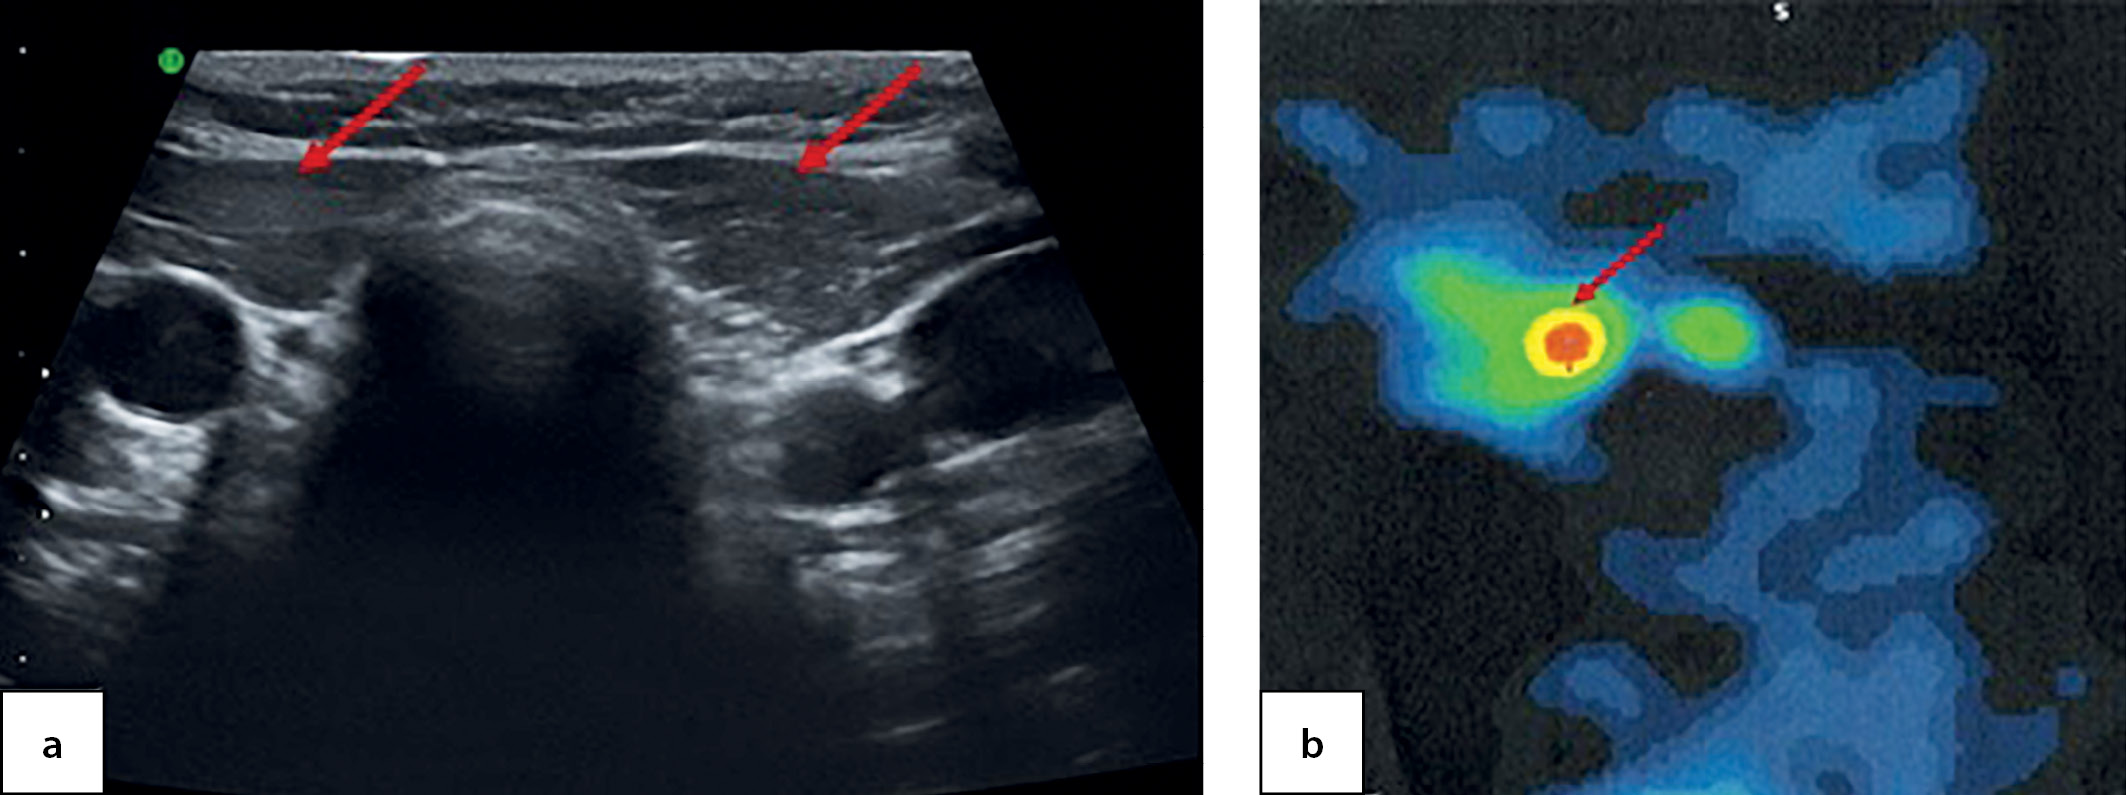

At the age of 6.5 the patient came to the National Endocrinology Research Centre for the first time. An ultrasound imaging found evidence of thyroid aplasia and identified a cyst in the right-hand side of anterior neck with dimensions 1.0×0.6×0.7 cm (Figure 4, a). Athyroid scintiscan confirmed the presence of a round-shaped residual ectopic thyroid tissue in the root of tongue and established its dimensions as 1.0×1.2×1.0 cm (Figure 4, b). The patient has continued to receive hormone therapy with 2.5 mg/kg/day levothyroxine.

Figure 4. An empty thyroid bed in a 6.5-year-old patient, identified through ultrasound imaging (a) and residual ectopic thyroid tissue in the root of tongue, as identified through a SPECT thyroid scintiscan with 99mТc pertechnetate (b)